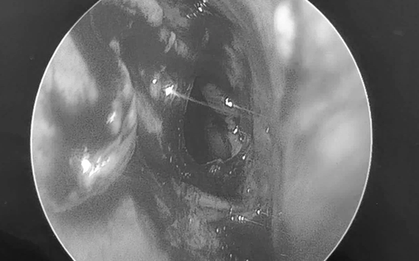

Ban đầu, bé trai được đưa vào bệnh viện để điều trị viêm phổi. Theo lời kể của cha mẹ bệnh nhi, họ chưa từng thấy bất kỳ dấu hiệu bất thường nào ở bé trước đó.